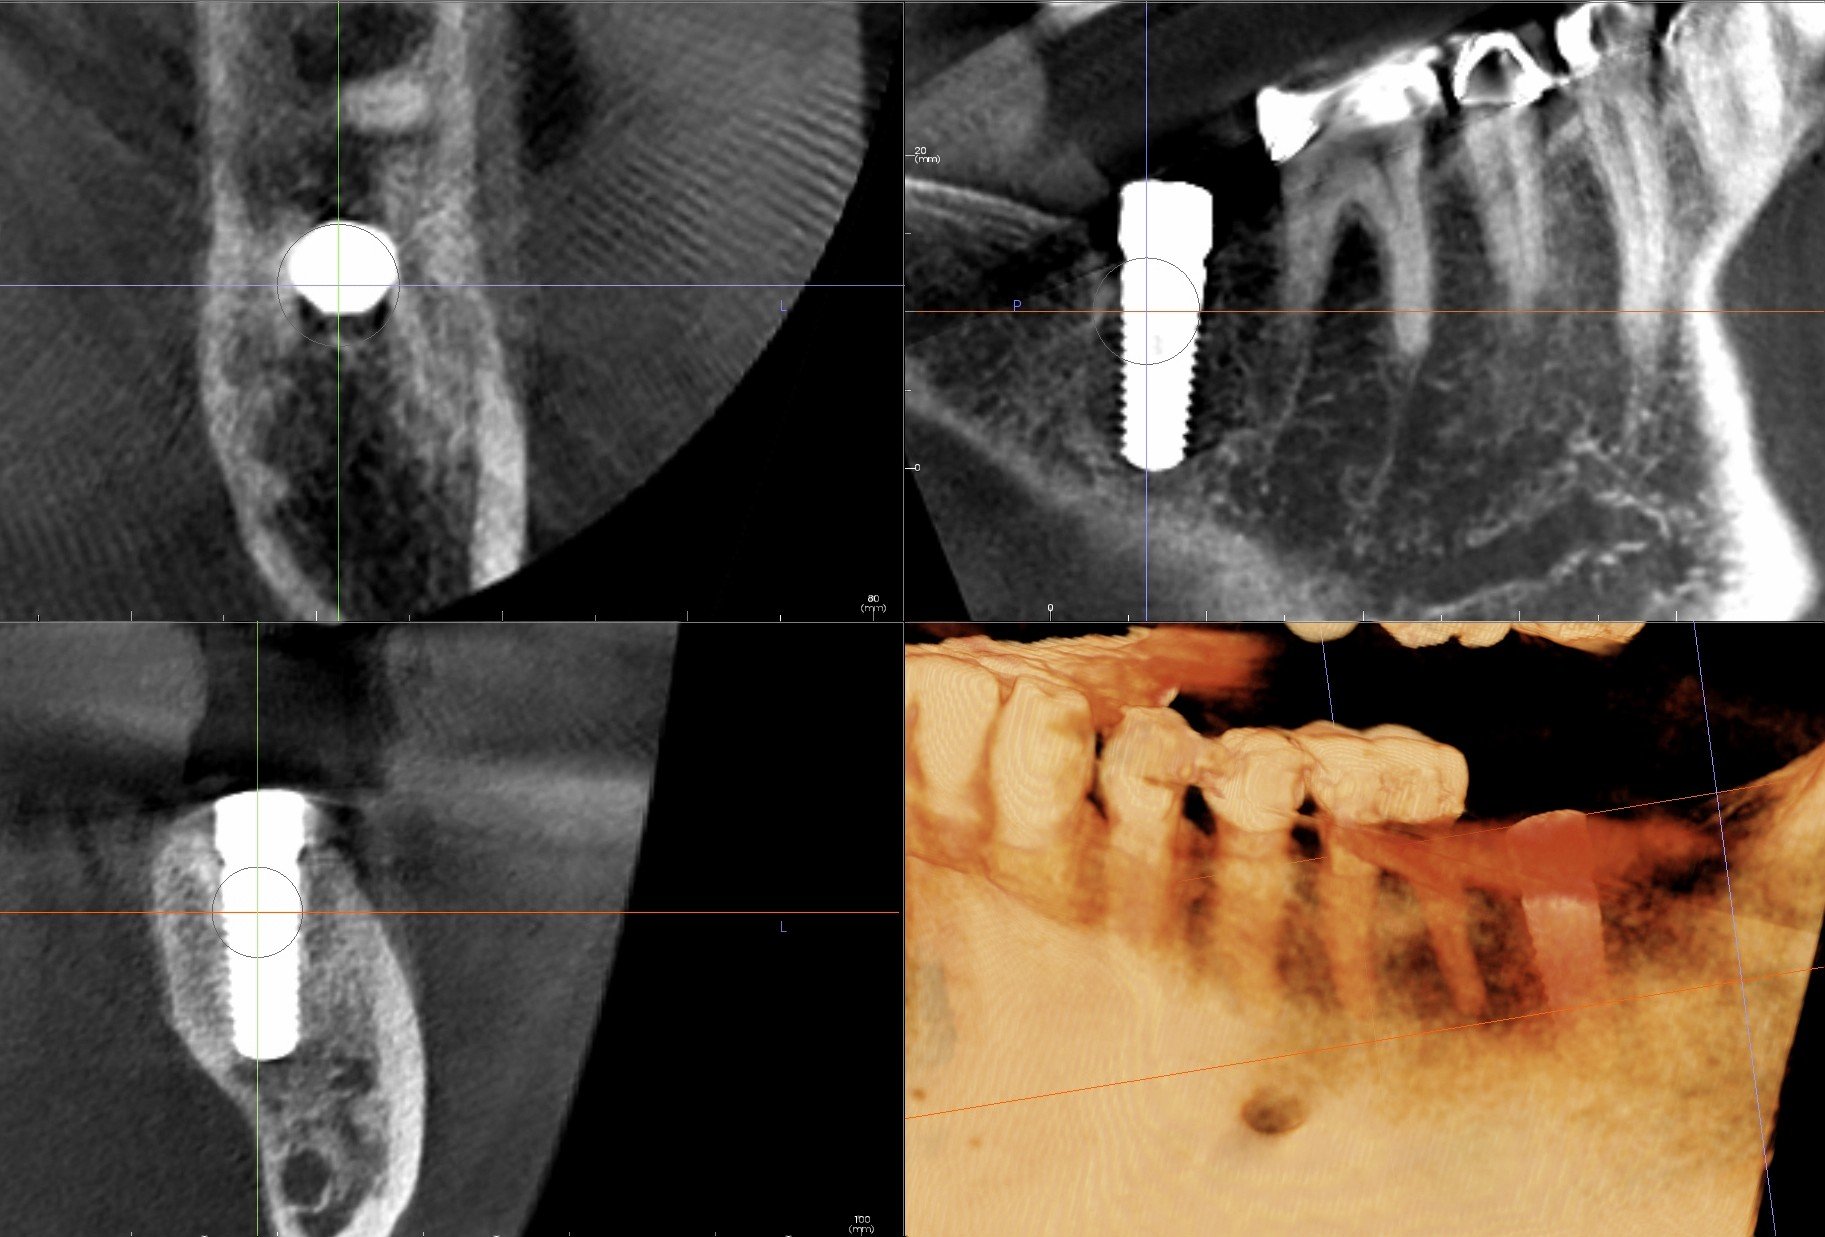

Second Molar Dental Implant 18 with Extraction and Bone Graft Ramsey